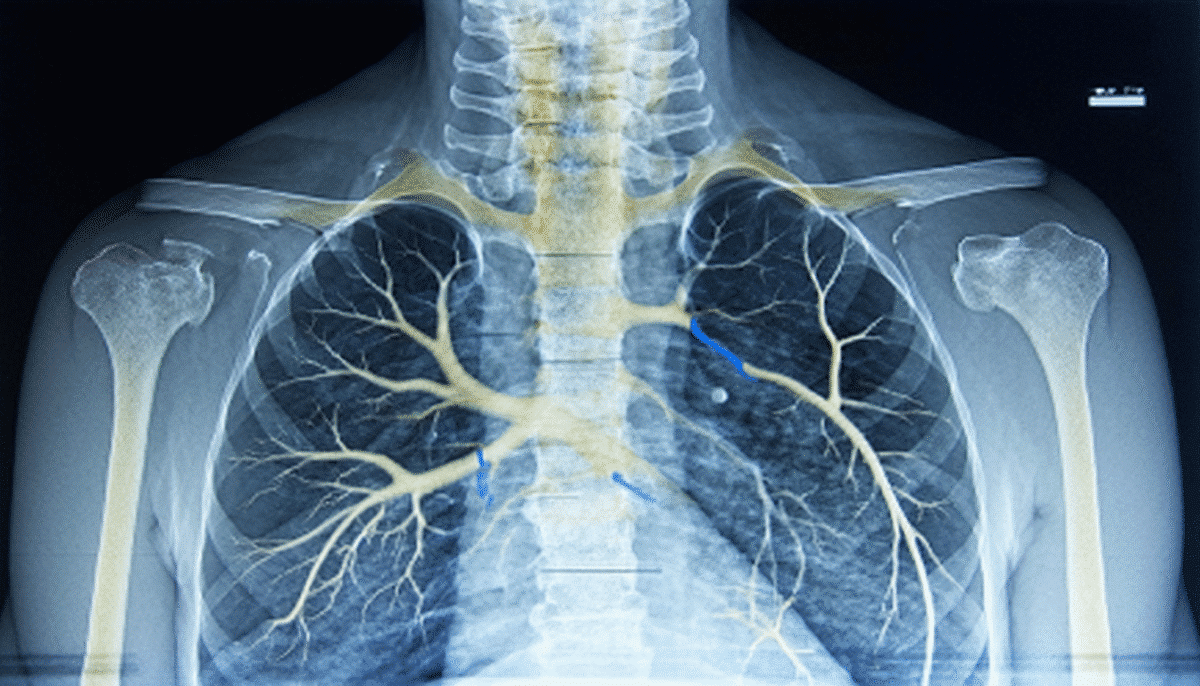

La « trame broncho-vasculaire » désigne le réseau visible des bronches et des vaisseaux sanguins pulmonaires qui irriguent les poumons. Sur une radiographie thoracique, ces structures forment un motif particulier, généralement fin et léger. Lorsque la trame est accentuée, cela signifie que ce motif devient plus dense et mieux défini, ce qui attire immédiatement l’attention du radiologue.

Cette accentuation peut être localisée, par exemple autour des zones péri-hilaires ou aux bases pulmonaires, ou bien être diffuse, impliquant une modification généralisée de la trame sur l’ensemble du champ pulmonaire. Ce constat peut correspondre à :

Pour illustrer, lors d’une bronchite aiguë, la paroi des bronches s’enflamme et s’épaissit, rendant plus visibles ces structures. Un autre exemple est l’œdème pulmonaire, où le liquide interstitiel s’accumule, amplifiant la trame vasculaire. Ces observations participent à l’élaboration d’un diagnostic respiratoire précis qui guidera la suite des investigations et traitements.

Le rôle essentiel de l’imagerie thoracique dans cette analyse ne doit pas être sous-estimé. Les rayons X classiques restent une première étape clé, facile d’accès, et capable de déceler ces modifications. Cependant, pour une meilleure définition surtout en cas d’accentuation marquée, le scanner thoracique s’impose. Sa capacité à offrir des images en coupes fines et une vision détaillée permet d’affiner les caractéristiques de la trame broncho-vasculaire accentuée ainsi que d’identifier d’éventuelles autres anomalies associées.